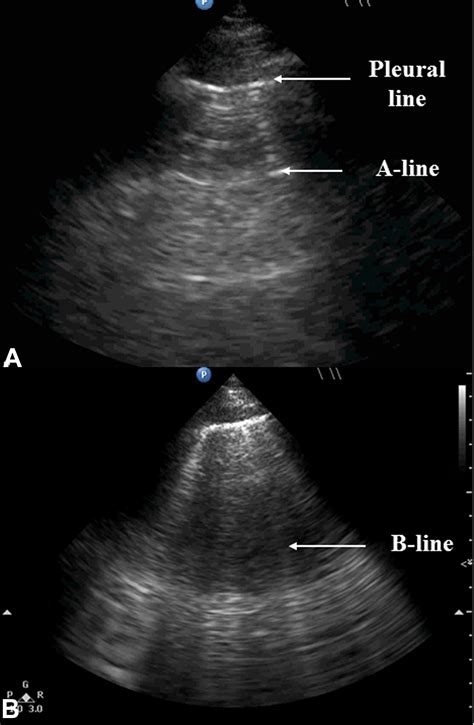

In the context of lung sonography, B Lines Ultrasound patterns are defined as discrete, laser-like vertical hyper-echoic reverberation artifacts. They arise from the pleural line and extend to the edge of the screen, moving in synchrony with lung sliding. Unlike A-lines, which represent normal horizontal reverberations caused by air-tissue interfaces, B-lines signify that the subpleural interlobular septa are thickened by fluid, cells, or fibrous tissue.

When these septa become edematous or infiltrated, they create an acoustic impedance mismatch that traps the ultrasound beam, resulting in the characteristic vertical "comet tail" appearance. Because they move with the visceral pleura, their presence is a highly sensitive marker for the loss of lung aeration.

The primary clinical value of identifying B Lines Ultrasound patterns lies in their ability to rule in or rule out interstitial syndromes. In an emergency setting, these findings are often used as a bedside tool to differentiate acute heart failure from chronic obstructive pulmonary disease (COPD) or asthma.

• Pulmonary Edema: Multiple B-lines are strongly associated with cardiogenic pulmonary edema.

The spatial distribution of B Lines Ultrasound artifacts provides vital diagnostic clues. If the artifacts appear symmetrically in gravity-dependent areas, clinicians should maintain a high suspicion for hydrostatic pulmonary edema (heart failure). Conversely, if the artifacts appear in a heterogeneous or patchy distribution, it is more indicative of multifocal pneumonia or non-cardiogenic causes such as pulmonary contusion.

When the B-lines are so numerous that they become "coalescent"—fusing together into a white, bright vertical band—this often indicates severe lung density. This finding is frequently seen in advanced pulmonary edema or severe ARDS, where the interlobular septa are so heavily filled with fluid that the ultrasound beam cannot distinguish individual septal lines.